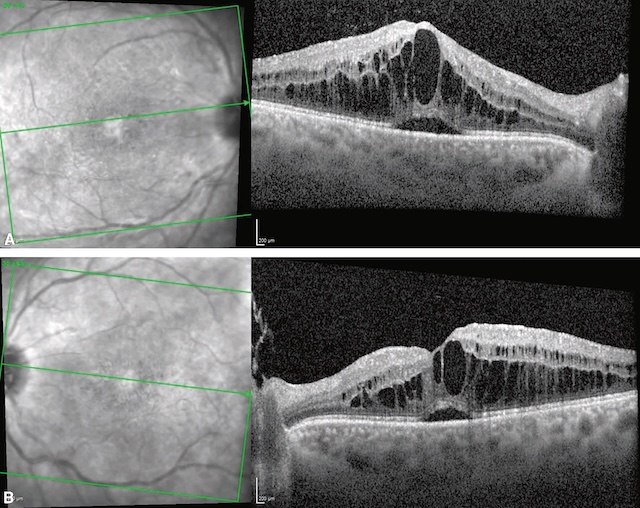

L’œdème maculaire se caractérise par une augmentation de l’épaisseur maculaire, associée à une baisse d’acuité visuelle en général progressive (fig. 7.8 et fig. 7.9A,B). Des métamorphopsies sont présentes, d’apparition insidieuse si la cause est chronique, ou aiguë si l’apparition de l’œdème est brutale. Lorsque l’œdème maculaire est important, il prend un aspect d’œdème maculaire cystoïde, qui donne une image très typique « en pétales de fleur ». En OCT, les kystes intrarétiniens sont nettement individualisables et expliquent le syndrome maculaire généralement présent dans ce type d’atteinte.

A. œdème maculaire diabétique dans sa forme diffuse. B. Cartographie OCT avec épaississement maculaire (couleurs chaudes jaune-rouge jusqu’au blanc). C. Logettes d’œdème intrarétinien visibles en OCT (flèches), responsable de la perte de l’aspect d’entonnoir fovéolaire « normal ». Noter un décollement séreux rétinien associé (astérisque).

Cette figure illustre un œdème maculaire diabétique à travers trois modalités d’imagerie. La partie A montre une photographie couleur du fond d’œil avec un épaississement maculaire central diffus. La partie B est une cartographie topographique rétinienne centrée sur la macula, en fausses couleurs, mettant en évidence une hyperépaisseur maculaire centrale en forme d’anneau concentrique, typique d’un œdème maculaire. La partie C correspond à une coupe OCT horizontale passant par la fovéa. Cette image montre des cavités kystiques intrarétiniennes hypo-réflectives situées dans les couches internes de la rétine, de part et d’autre d’un épaississement fovéal marqué (indiqué par des flèches). Une cavité centrale plus importante est marquée par un astérisque.

Deux images en tomographie en cohérence optique (OCT) illustrent un œdème maculaire diabétique. Dans chaque ensemble, l'image de gauche montre une photographie infrarouge de la rétine avec repérage des coupes OCT par des lignes vertes. Les images de droite représentent les coupes OCT correspondantes. Sur les coupes transversales, on observe une augmentation de l'épaisseur rétinienne avec de multiples espaces kystiques intrarétiniens bien délimités.